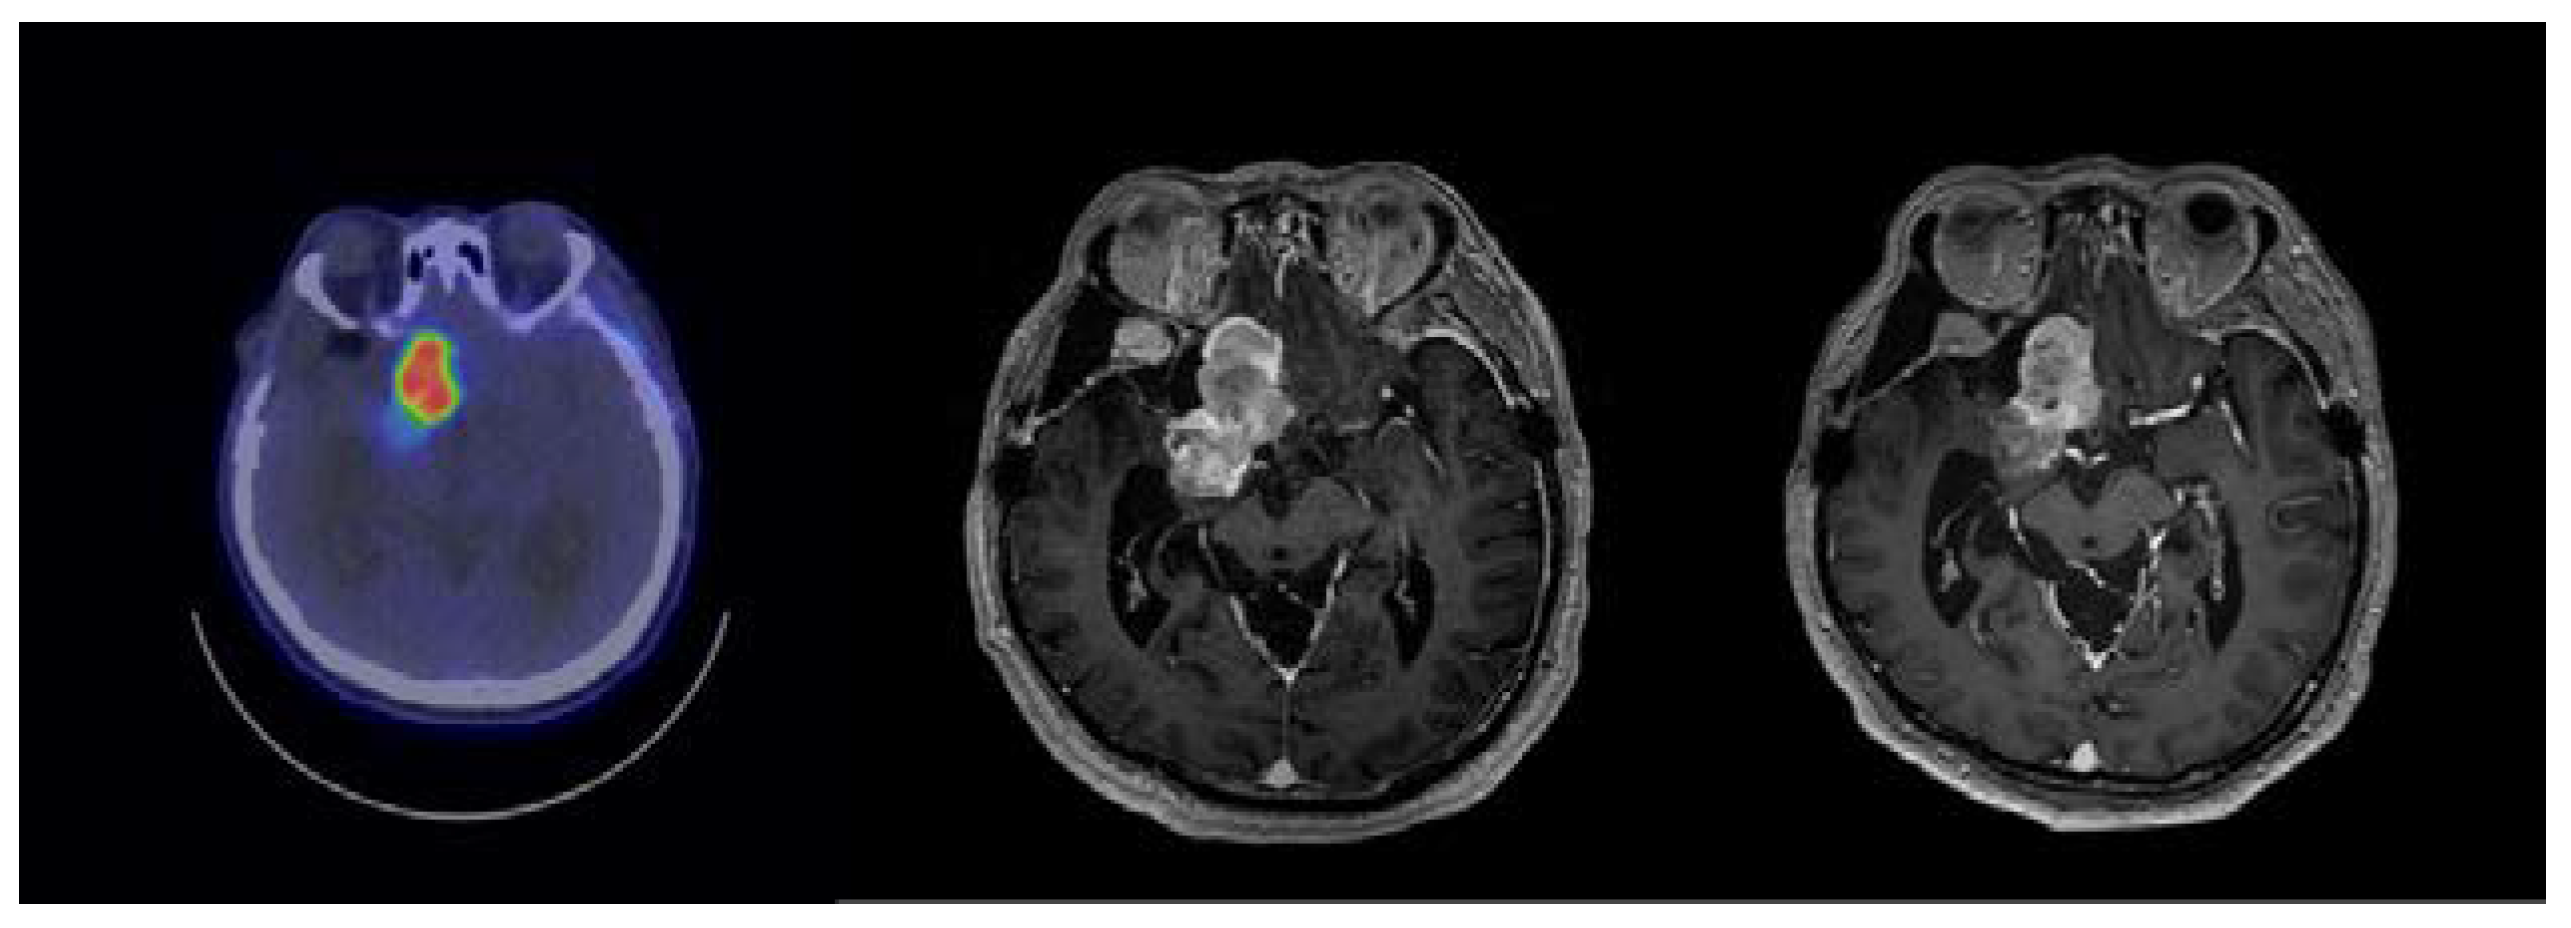

2.1. Case 115

2.2. Case 191

2.3. Case 197

2.4. Case 284